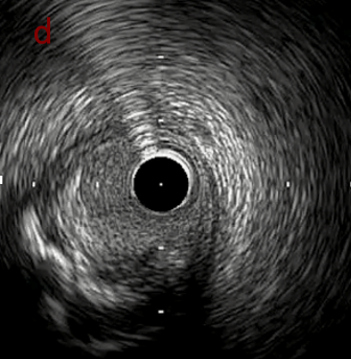

IVUS after OAS low speed 3回

IVUS imaging after low speed 3回

OAS low speedによる引きのsandingを3回行いIVUSを確認するとa-cでは心筋側側へのOASによる良好なbias変化と、それに伴いdの健常側への危険なbias変化を認めた。

そのためcでIVUSマーキングを行い、その点より引きで赤線のpinpoint OAS high speedを行い、dに関してはinjury回避のためにOASを当てない方針とした。